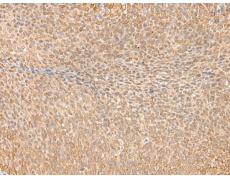

IHC positive control: |

Human gastric cancer and human tonsil |